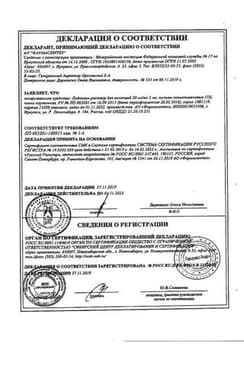

Сертификаты